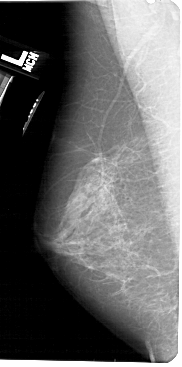

A_1520_1.LEFT_CC

LEFT_CC LINES 5416 PIXELS_PER_LINE 2701 BITS_PER_PIXEL 12 RESOLUTION 43.5 NON_OVERLAY